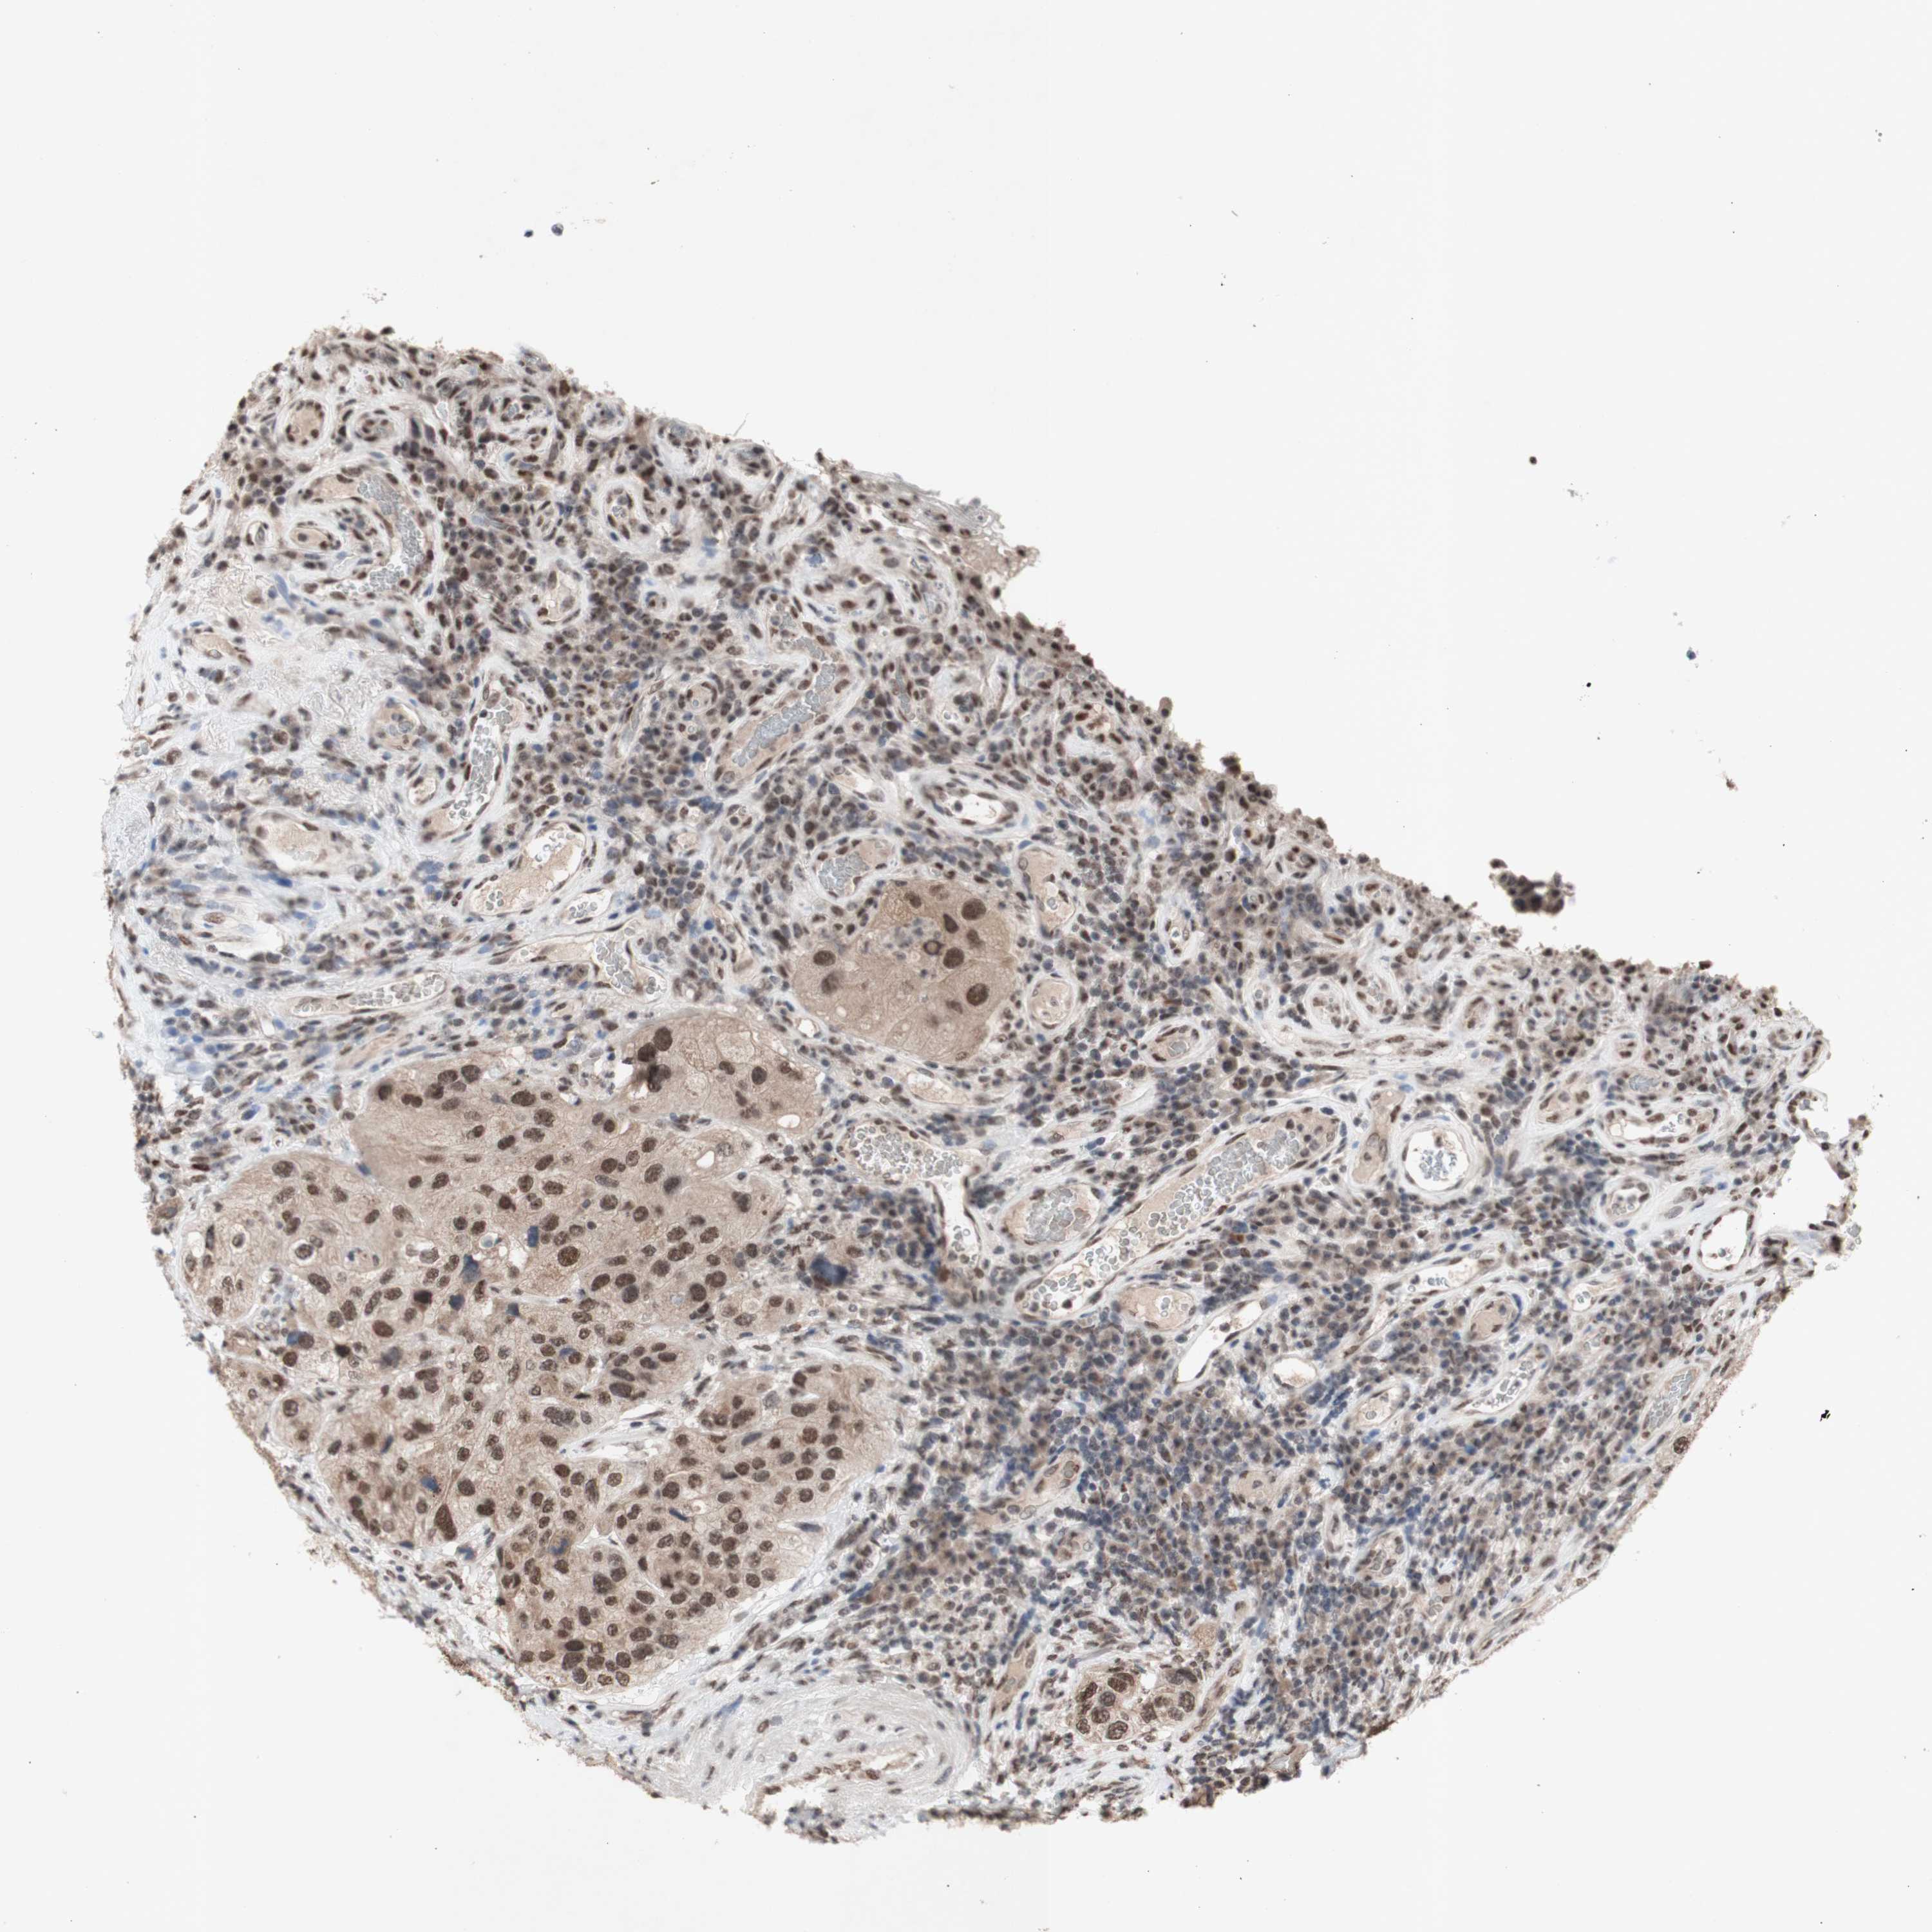

UROTHELIAL CANCER - Protein expressioni

A mouse-over function shows sample information and annotation data. Click on an image to view it in a full screen mode. Samples can be filtered based on level of antibody staining by selecting one or several of the following categories: high, medium, low and not detected. The assay and annotation is described here.

Note that samples used for immunohistochemistry by the Human Protein Atlas do not correspond to samples in the TCGA dataset.

Antibody stainingi

Antibody staining in the annotated cell types in the current human tissue is reported as not detected, low, medium, or high, based on conventional immunohistochemistry profiling in selected tissues. This score is based on the combination of the staining intensity and fraction of stained cells.

Each image is clickable and will lead to virtual microscopy that enables deeper exploration of all samples and also displays staining intensity scores, fraction scores and subcellular localization as well as patient and tissue information for each sample.

Antibody HPA047513

Antibody HPA054689

Antibody CAB009886

Staining

High

Medium

Low

Not detected

Intensity

Strong

Moderate

Weak

Negative

Quantity

>75%

75%-25%

<25%

None

Location

Nuclear

Cytoplasmic/membranous

Cytoplasmic/membranous,nuclear

Urothelial carcinoma, High grade

Urothelial carcinoma, Low grade